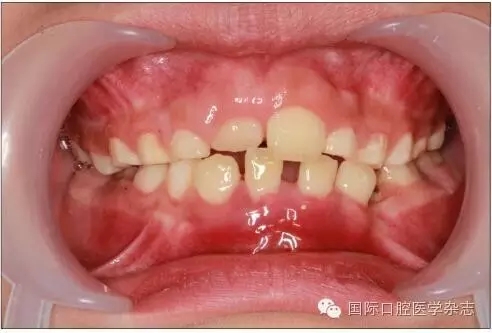

牙齒異位萌出是指恒牙在萌出過程中,未在牙列的正常位置萌出,兒童口腔臨床最常見的是上頜第一恒磨牙和上頜尖牙的異位萌出。造成第一恒磨牙異位萌出的原因包括:第二乳磨牙和第一恒磨牙的牙冠體積較大;頜骨的發(fā)育不足,尤其是上頜結(jié)節(jié)發(fā)育不足;第一恒磨牙的萌出角度異常,牙軸向近中傾斜等,歸根結(jié)底是在第一恒磨牙萌出階段出現(xiàn)了牙量和骨量不調(diào)的問題,頜骨發(fā)育不足是最主要的原因。發(fā)生率為2%~6%,男性多于女性,其中2/3發(fā)生在上頜,可單側(cè)或雙側(cè)對稱出現(xiàn)。第一恒磨牙的異位萌出常常造成第二乳磨牙早失,牙弓長度減小。臨床上,常用分牙簧分離第一恒磨牙與第二乳磨牙,或使用恒磨牙面粘著舌扣的Halterman矯治器,或變異Nance弓推第一恒磨牙向遠中的方法,改變恒牙萌出道,阻斷恒磨牙對乳磨牙的壓迫吸收,引導(dǎo)恒磨牙正常萌出。圖7顯示為一左上第一恒磨牙異位萌出的患兒,左上第二乳磨牙松動,牙弓長度減少[6]。

左:口內(nèi)照;右:全景片。

圖7 左上第一恒磨牙異位萌出,左上第二乳磨牙松動

Fig 7 Ectopic eruption ofleft upper the first permanent molar, loose of left upper the second primarymolar